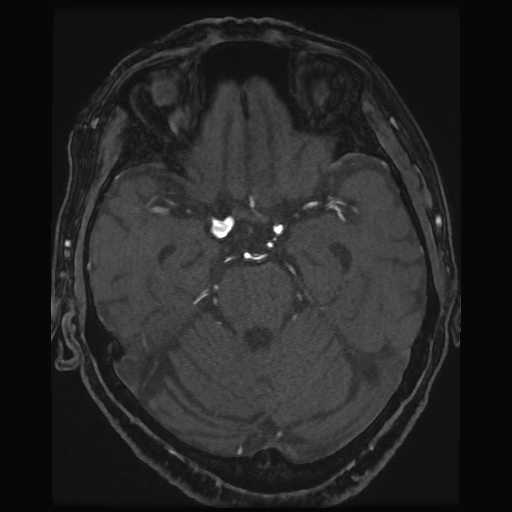

頭部

脳動脈瘤